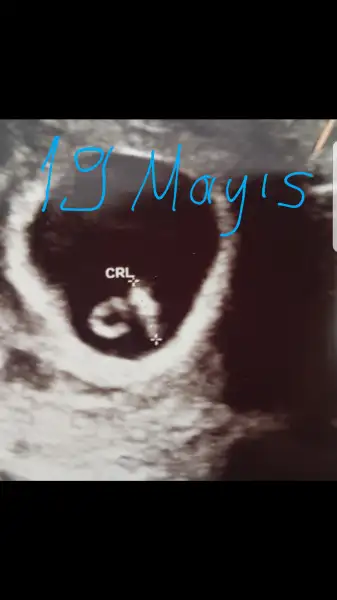

Ben bugün usg ye girdim. Dün gece ağrı ile uyandım. Yarım saat aynen adet sancısı gibi kıvrandım. Düşüyor mu acaba diye de düşündüm. Tek umudum lekelenme olmayışı oldu. Kontrolüm normalde yarındı. Ama bi uğradım doktora ağrım oldu diye sormaya "Büyüyordur" dedi. Usg den baktık kese büyümüş biraz daha dedi. İçinde de nokta var. Ümit olması için yüklüyorum. Rabbim kucaklarımızı hayırlı sağlıklı evlatlarla doldursun inşallah.